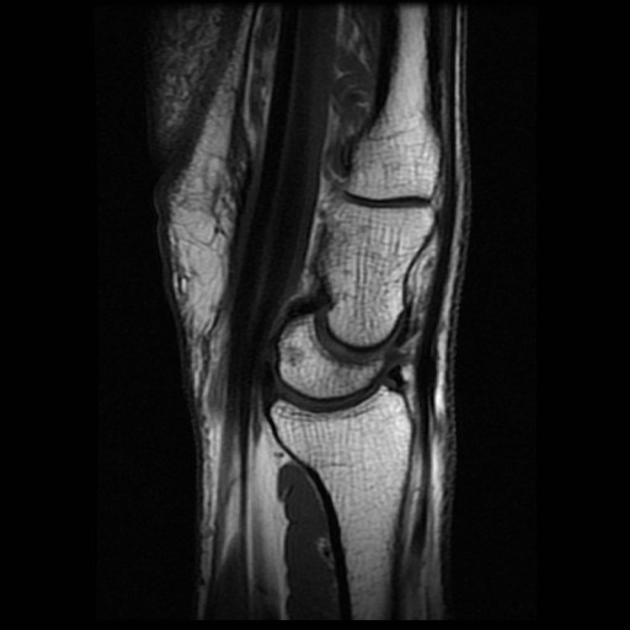

Diagnosis?

What must be intact for this appearance to occur?

Bucket handle meniscal tear (80% are medial meniscus). Highly specific but variable sensitivity for bucket handle tear.

The ACL must be intact for the tear to look like this- in order to prevent the fragment from migrating further laterally.